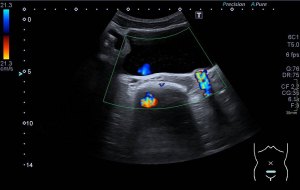

Los vientres anteriores de los Músculos Digástricos derecho e izquierdo forman los bordes laterales del triángulo submentoniano, mira:

En este triángulo lo que vas a encontrar son ganglios.